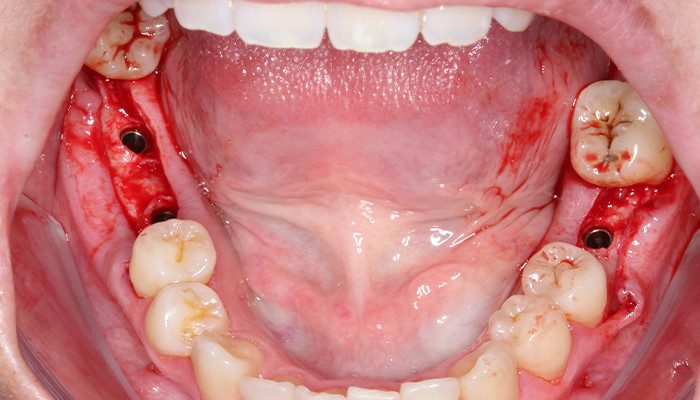

2 e 3 | Aspecto inicial intraoral.

4 | Retalho de espessura total.